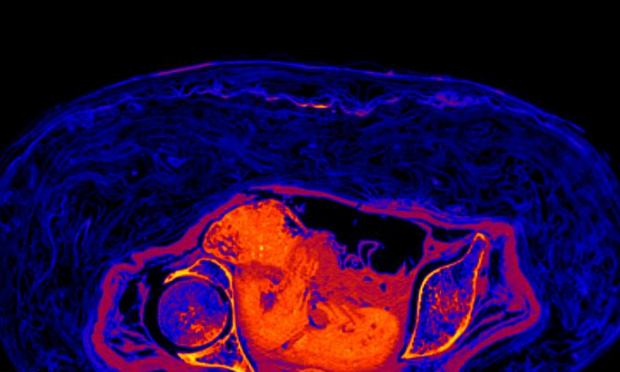

Το έμβρυο στη μουμιοποιημένη αιγυπτιακή μούμια, που ανήκει στο Πανεπιστήμιο της Βαρσοβίας και φυλάσσεται στο Εθνικό Μουσείο της Βαρσοβίας, έχει επιβιώσει μέχρι την εποχή μας λόγω μιας πολύ ασυνήθιστης διαδικασίας αποσύνθεσης. -“Ήταν παρόμοιο με αυτό που ήταν γνωστό από την ανακάλυψη προϊστορικών σωμάτων στους βάλτους” – πιστεύει μια ομάδα Πολωνών ερευνητών. Ήδη το 2016, οι ίδιοι ειδικοί διαπίστωσαν ότι η μούμια που αποδίδεται στον ιερέα Hor-Dżehuti, κρύβει στην πραγματικότητα το ταριχευμένο σώμα μιας γυναίκας. Ένα τέτοιο συμπέρασμα ήταν δυνατό χάρη στη χρήση ενός σύγχρονου τομογράφου, επειδή η μούμια είναι ακόμα πλήρης – οι επίδεσμοι δεν αναπτύχθηκαν για ερευνητικούς σκοπούς.

Τώρα οι επιστήμονες εξέτασαν προσεκτικά το έμβρυο και τη μορφή με την οποία έχει επιβιώσει μέχρι την εποχή μας και δημοσίευσαν τα συμπεράσματά τους στο Journal of Archaeological Science. Για άγνωστους λόγους, το έμβρυο δεν αφαιρέθηκε από τη μήτρα κατά τη διάρκεια της μουμιοποίησης. Ωστόσο, τα εσωτερικά όργανα της Αιγύπτιας αφαιρέθηκαν.

Όπως είπε μια ανθρωπολόγος και αρχαιολόγος, συν-διευθύντρια του Warsaw Mummy Project Marzena Ożarek-Szilke, η οποία είναι μία από τις συγγραφείς του άρθρου, οι εικόνες δείχνουν ότι η εμβρυϊκή μούμια διατηρήθηκε χάρη σε μια πολύ ασυνήθιστη διαδικασία.

Προς το παρόν, έχει διαπιστωθεί ότι το έμβρυο είναι κουλουριασμένο στην εμβρυϊκή θέση. Το φύλο του είναι άγνωστο. Σύμφωνα με τη συν-συγγραφέα του άρθρου, γιατρό Katarzyna Jaroszewska, γυναικολόγο-μαιευτήρα, το κανάλι γέννησης της νεκρής μητέρας δεν ήταν ανοιχτό. Σημαίνει, λοιπόν, ότι η αιτία θανάτου της γυναίκας δεν σχετιζόταν με τον τοκετό και τις επιπλοκές του. Αυτό επιβεβαιώνει και τη θέση του εμβρύου.